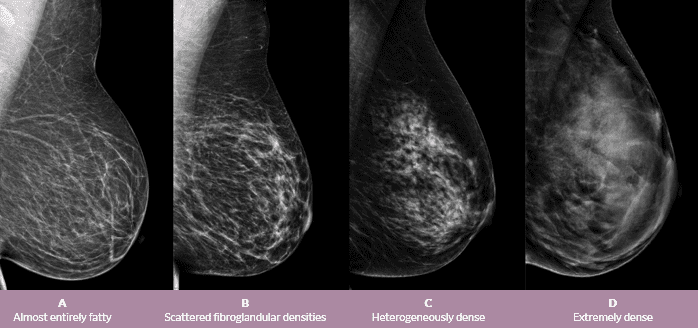

Included is detail on checking yourself and when to see a doctor. Fast facts on breast cancer in teens: Tip cancerous lumps are more likely to be hard, painless, and unmovable. One study by the university of southern california found that breastfeeding seems to lower the risk of breast. When breast cancer is detected early, less aggressive treatment is needed and the chance of survival is higher. Simply put, breast cancer screening refers to the regular breast exams recommended by doctors to detect breast cancer before symptoms develop. Breast cancer is the most common cancer among women. Warning this video does not replace actual medical advice. Think twice about oral contraceptives. Screening for breast cancer includes activities which test members of asymptomatic populations for breast cancer. No imaging modality always detect breast cancer. Early detection methods for breast cancer include screening mammography, clinical breast examination (carried out by a trained health professional) and breast awareness. Brca1 and brca2 are examples of genes that raise your cancer risk if they become altered.